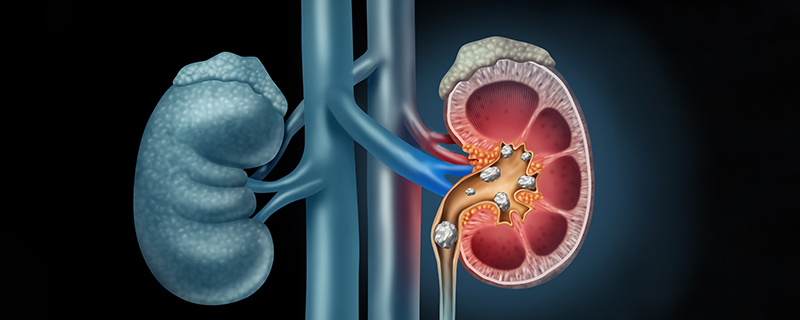

요로결석은 비뇨기관에서 소변의 성분들이 결정으로 변하여 돌이 형성되는 질병입니다.

요로결석은 소변이 만들어져 배출되는 길인 요로에 결석이 생기는 질환입니다. 결석은 주로 칼슘, 수산염, 인산염 등의 무기질이 소변에 녹지 못하고 결정으로 뭉쳐져 생성됩니다.

요로결석은 신장, 요관, 방광, 요도 등 어디에서나 생길 수 있지만, 가장 흔하게는 요관에서 생깁니다. 요관은 신장에서 방광으로 소변을 운반하는 관으로, 지름이 약 5mm 정도입니다. 결석이 요관에 생기면 통증, 구역질, 구토, 혈뇨 등의 증상이 나타날 수 있습니다.